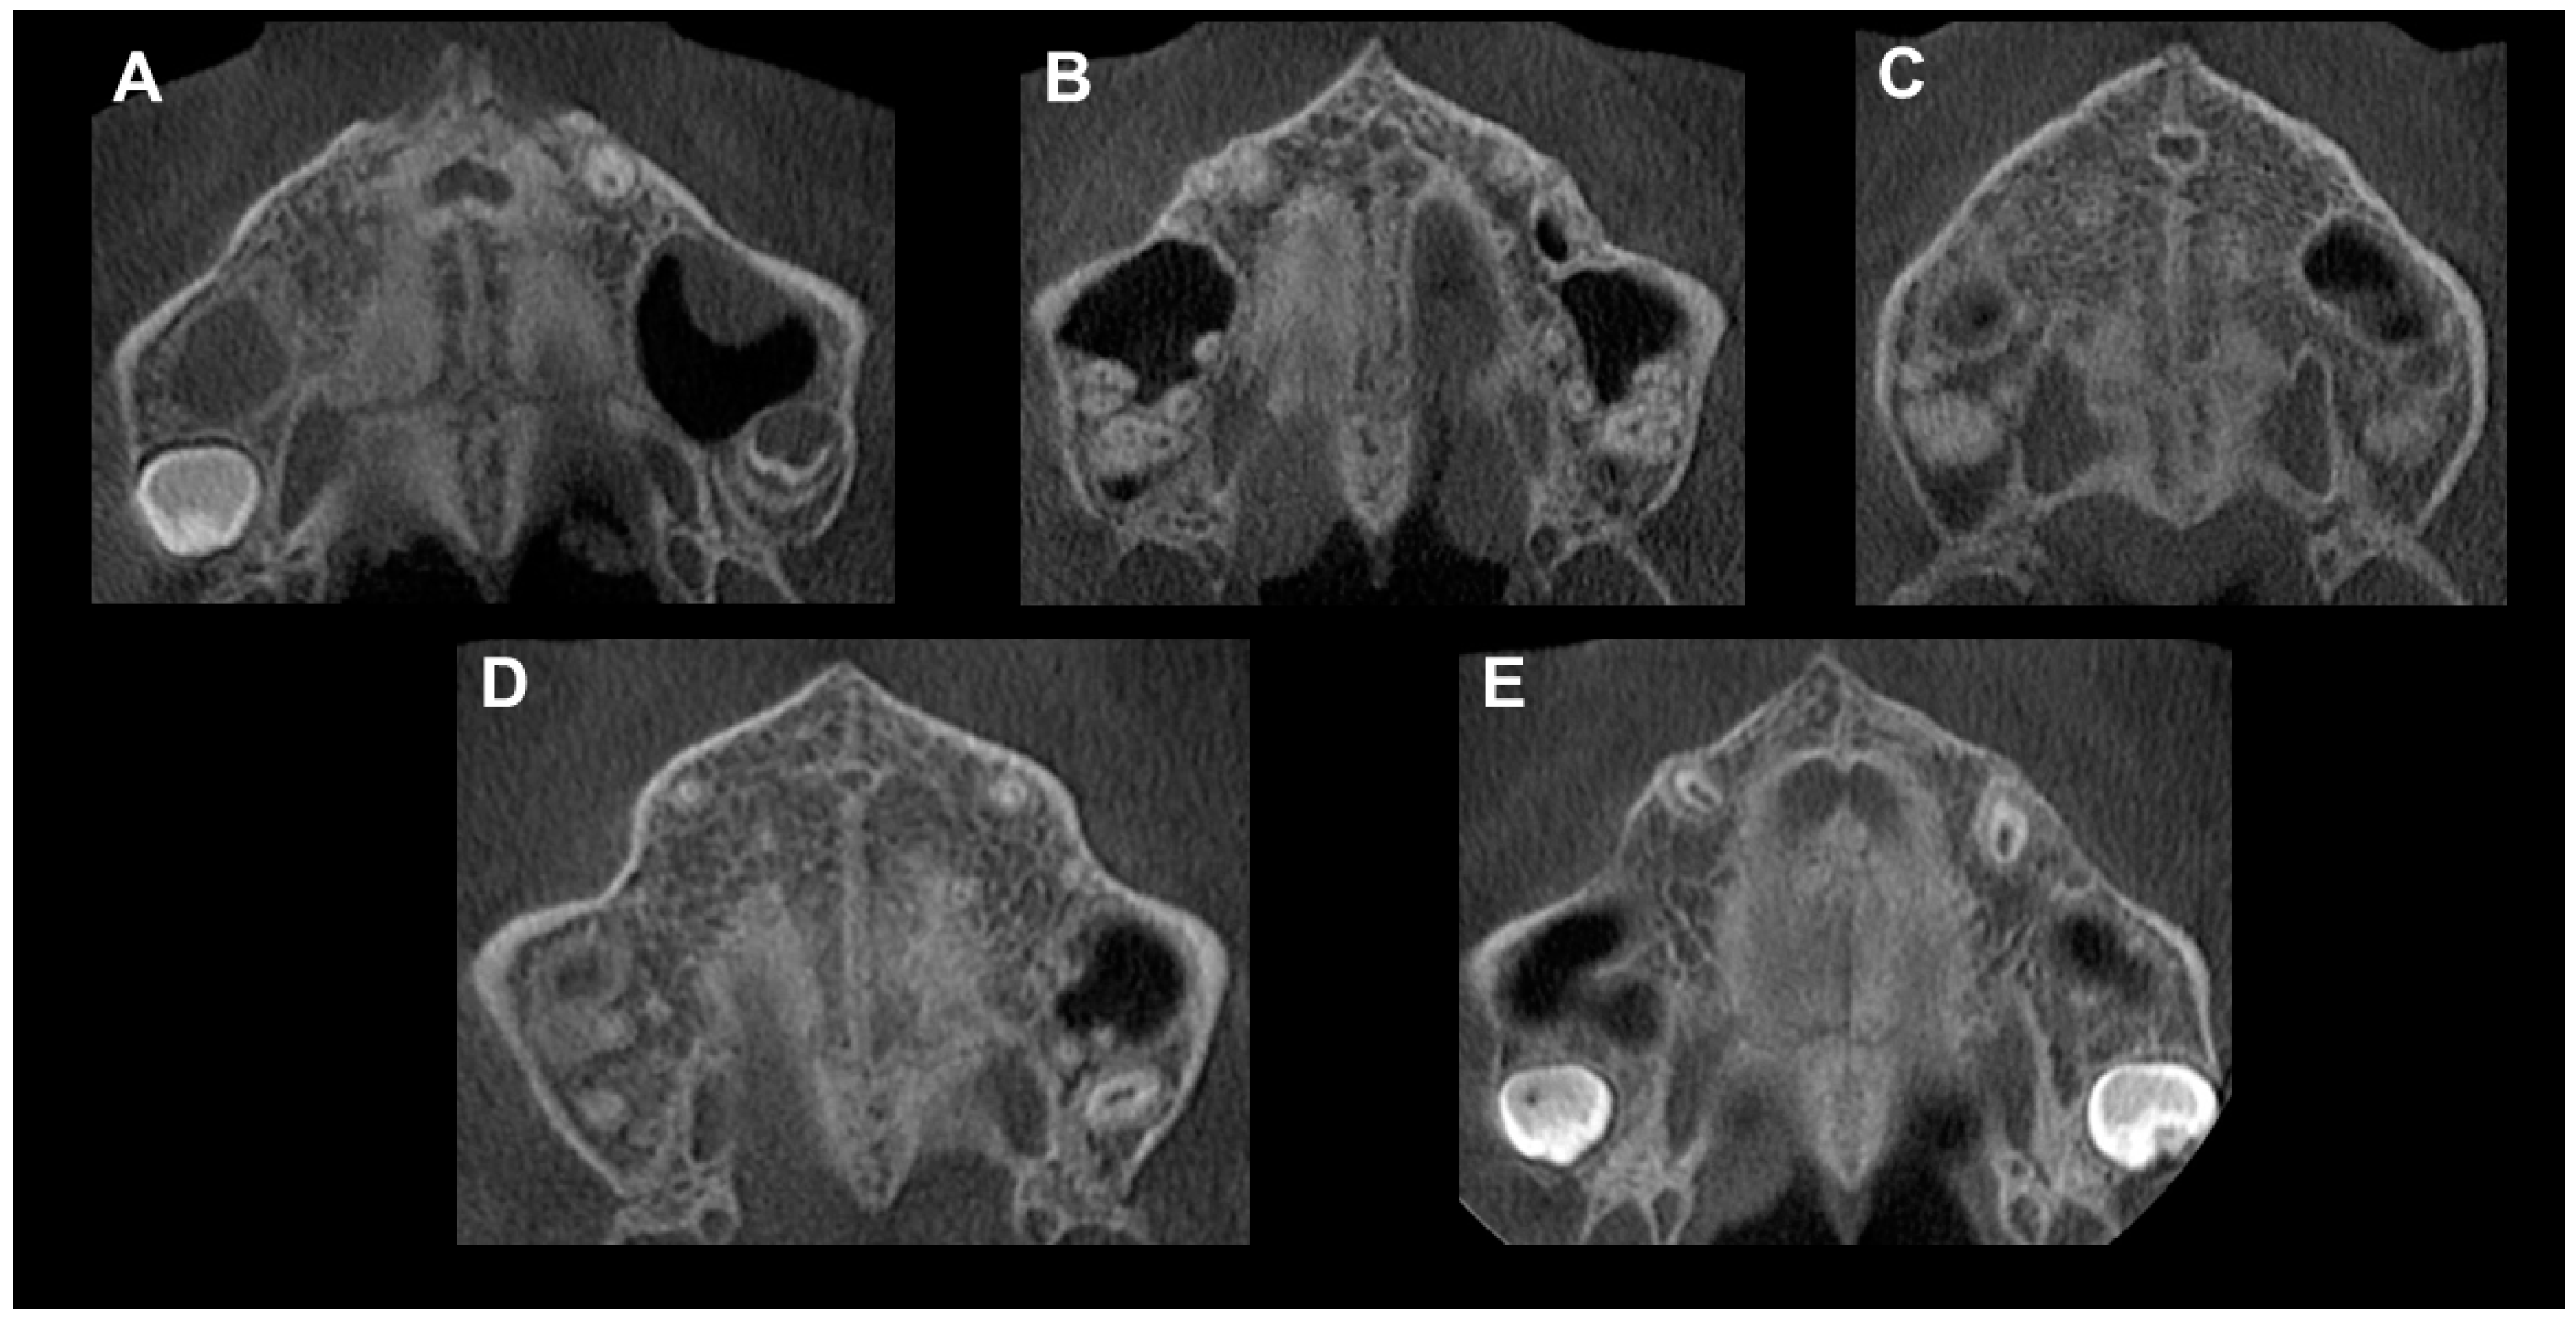

Figure 3.

Method of Angelieri et al. [40] in CBCT. (A) The midpalatal suture is seen as a relatively straight radiopaque line. (B) The midpalatal suture appears as a scalloped line of high density. (C) Two radiopaque, scalloped and parallel lines are separated by areas of low radiographic density. (D) The palatine bones become more radiopaque, and the suture is not visualized in this sector; it is only visualized as two scalloped high-density lines at the midline on the palate bone. (E) It is no longer possible to see the suture along the maxillary and palatine bones, which indicates that fusion has occurred in the maxilla.